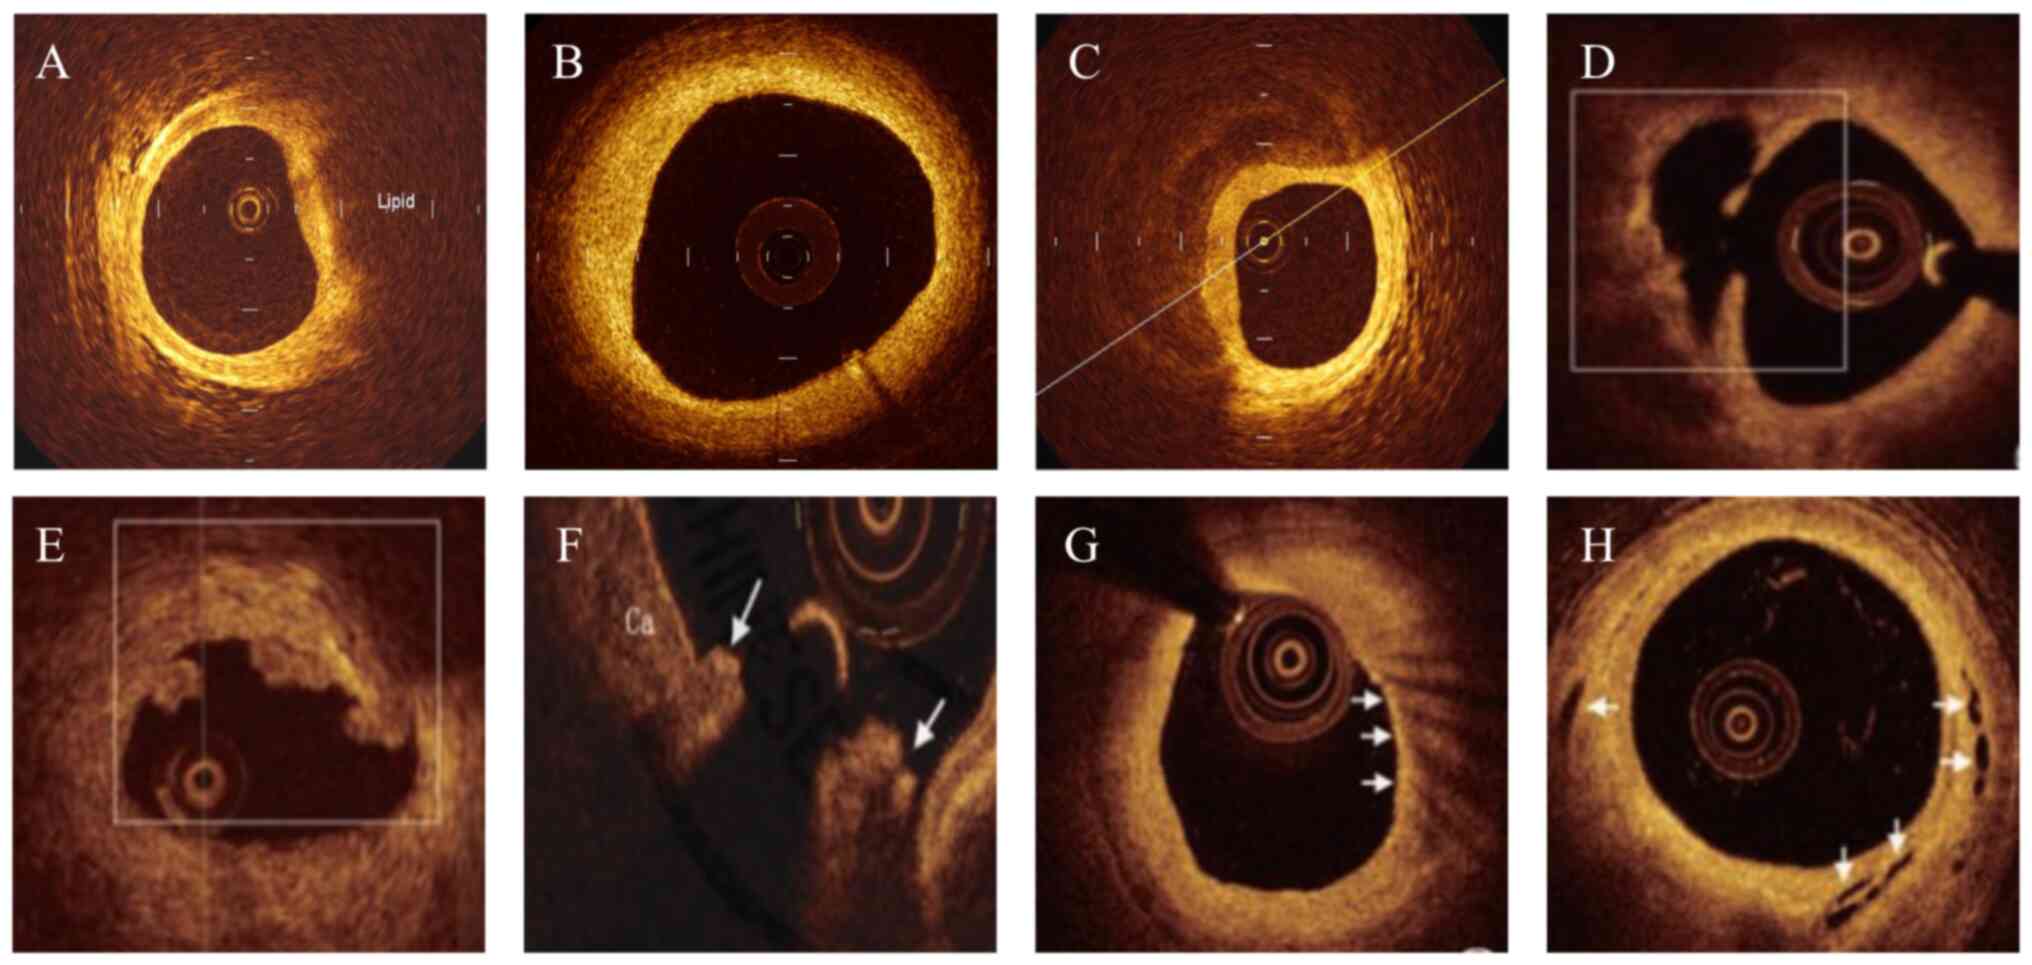

OCT examination

The intravascular OCT imaging system (model no. C408661; OPTIS™ Mobile System; Abbott Medical) was used to analyze the morphological characteristics of culprit plaques. All OCT images were analyzed by two experienced researchers who were blinded to the coronary angiography data and clinical manifestations (HS and HY). When the opinions of the two researchers differed, a third researcher was asked to evaluate such research and reach a consensus through discussion (SD). Quantitation of plaque composition included lipid plaque (heterogenic, signal-poor, highly attenuating intimal regions with diffuse or poorly defined border; Fig. 1A), fibrous plaque (high backscattering and homogeneous signal-rich region; Fig. 1B) and calcified plaque (signal-poor or heterogeneous region with a sharply delineated border; Fig. 1C) (18). In the present study, the culprit lesion was categorized into plaque rupture, plaque erosion or calcified nodule (19). Plaque rupture was defined as the presence of fibrous cap discontinuity and cavity formation in the plaque (Fig. 1D), plaque erosion was characterized by a lesion with attached thrombus overlying an intact fibrous cap (Fig. 1E) and calcified nodule was defined as an accumulation of nodular calcification with disruption of the fibrous cap on the calcified plate (arrowheads, Fig. 1F).

Figure 1

Optical coherence tomography images. (A) Lipid plaque; (B) fibrous plaque; (C) calcified plaque; (D) plaque rupture; (E) plaque erosion; (F) calcified nodule; (G) macrophage accumulation; (H) microchannels.

The plaque features of vulnerability were also evaluated, including lipid length, minimum fibrous cap thickness, lipid arc, macrophage accumulation and microchannel (20). Lipid length was obtained on the longitudinal view, minimum fibrous cap thickness was measured three times at the thinnest part and the average value was calculated, and lipid arc was measured at every 1 mm interval throughout the entire length of lipid length. Subsequently, lipid index was calculated as the product of lipid length and mean lipid arc, and thin-cap fibroatheroma (TCFA) was defined as a lipid-rich plaque with a minimum fibrous cap thickness <65 um. Macrophage accumulation was characterized by increased signal intensity within the fibrous cap, accompanied by heterogeneous backward shadows (arrowheads, Fig. 1G), and microchannel was defined as a black hole or tubular structure within a plaque observed on ≥3 consecutive cross-sectional images (arrowheads, Fig. 1H). For patients with plaque rupture, the cross-sectional area (CSA) of the lumen was measured at the largest plaque site. Healed plaques were defined as plaques with ≥1 signal-rich layers of different optical density (21).